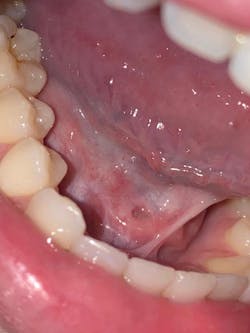

A 19-year-old female presented to our clinic with a complaint of swelling and pain from the lower right mandibular area, as well as sharp pain below her tongue. Examination revealed a swollen right submandibular gland and significantly enlarged Wharton’s duct papillae, with an area approximately 4 mm wide of calculi seen within the duct (figures 1 and 2).